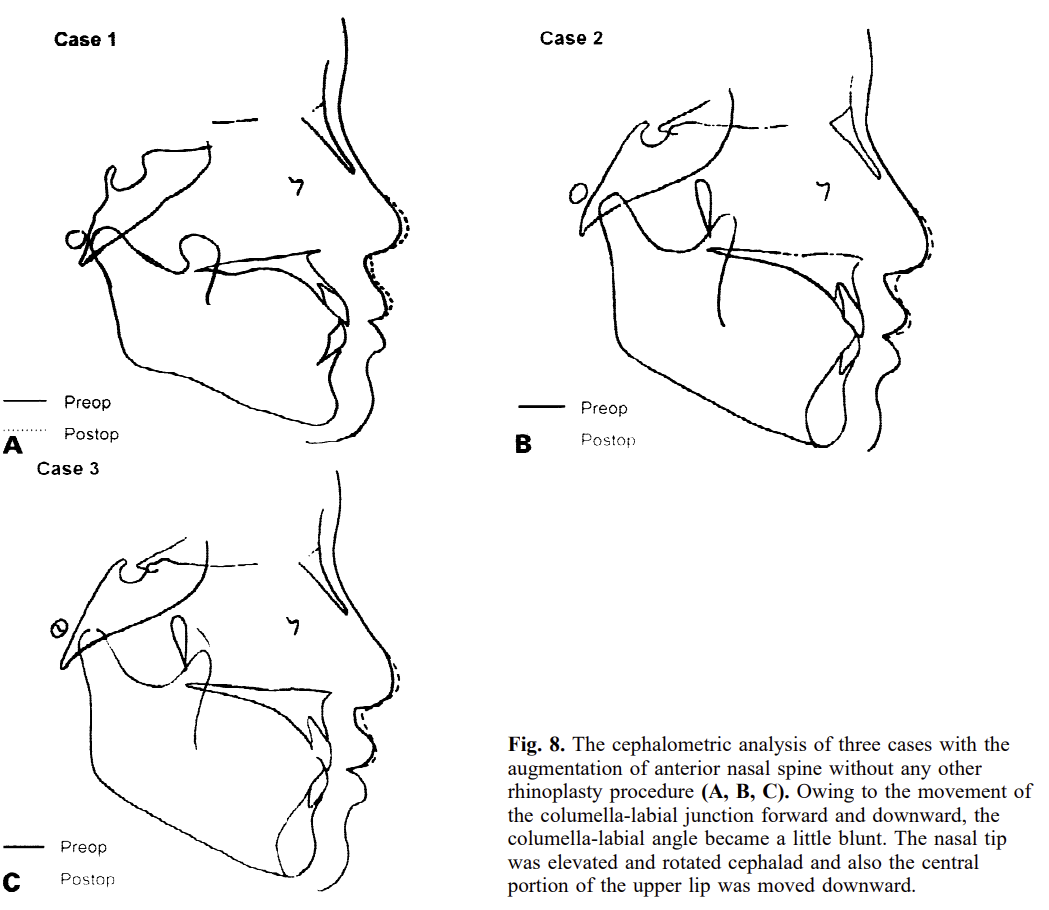

2. Cartilage or bone graft

- Cartilage, or a bone plate is harvested.

- A small graft is placed directly on the ANS.

- Recommended to be done during a rhinoplasty.

- This approach is usually paired with a projection rhinoplasty, where the surgeon grafts the dorsum, tip, and ANS. It is common in Asia and often gives great results. The extra nose projection pulls midface soft tissue forward, making the transition from the maxilla to the nose smoother whilst giving the illusion of forward growth.

The last example is especially impressive, earlier examples had grafts along the whole nose, this one used a single graft on the ANS and still pushed the nasal base forward, proof that you can fix ANS projection without touching the rest of the nose.